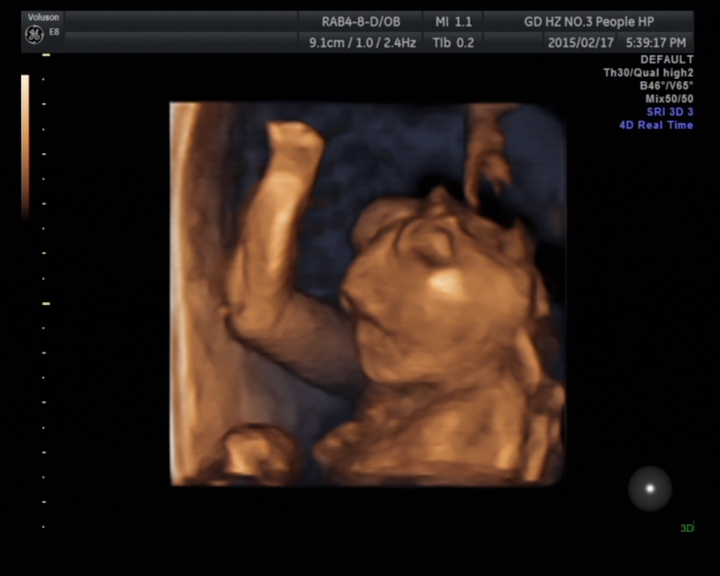

故事发生于2015217号(年廿九)下午,一对年轻的夫妇满脸笑容地向超声科走来,准妈妈怀孕约21周,来医院做胎儿彩超检查,想着明天回家开开心心过新年。谁知道天有不测风云,张春云副主任医师在检查中发现胎儿患有先天性畸形——无脑儿、复杂性心脏畸形、唇腭裂。就在那一瞬间,一切都变了,她哭了,他也变得心情沉重,脸上也失去了笑容。

无脑畸形是指胎儿颅盖骨缺失。具体病因不明,可能与脊柱裂相似,也是多因素致病,包括遗传、环境、致畸因子如射线、水杨酸盐、磺胺等。无脑儿表现为无颅盖、无大脑,仅见颅底或颅底部分脑组织,双眼眶位于最高处,无额骨显示,呈“青蛙”状面容。无脑儿一般不能存活,少数生出来后能存活几个小时或一天。因此,一旦超声明确诊断,将立即终止妊娠。